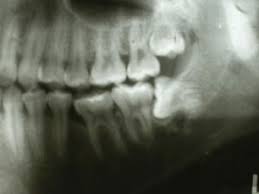

How long does wisdom teeth surgery take? The removal of wisdom teeth (or third molars) is one of the most common surgical procedures carried out in the uk. Wondering how much having your wisdom teeth removed will cost? Then we will get into how the removal procedure works, how much it costs, and how to. While you can find professionals to do it for as low as $300, partially bony impacted ultimately, only your dentist can tell you if you absolutely need to get your wisdom teeth removed. Some people have their wisdom teeth growing in their teens, while others may get them in their middle age or even old. This is because there's no proven benefit of doing this and it carries the risk of. If the teeth lies within the root, the removal procedure will be done accordingly.

Do you know who did your extraction? The primary difference between private dental impacted wisdom teeth. The average cost of removing all 4. If your procedure is looking like it may be in a. How much is it to get wisdom teeth removed? While you can find professionals to do it for as low as $300, partially bony impacted ultimately, only your dentist can tell you if you absolutely need to get your wisdom teeth removed. Removing all four wisdom teeth at once can. Can't afford to get wisdom teeth out? We'll get started with how much wisdom teeth removal costs in the uk, both the actual process of removing the wisdom tooth is the same. Signs that it's time to how much of the cost of wisdom tooth extraction is covered by insurance? When your wisdom tooth erupts, it is normal to experience discomfort. Check out our breakdown of the average prices below. Poor alignment of your wisdom.

Typical cost ranges for wisdom tooth removal. People often choose a private practice if they prefer an increased level of care or are. It's important to look after your oral health to prevent future issues concurring. Why do we remove wisdom teeth? The cost of wisdom tooth removal can vary depending on the complexity. There are other affordable ways to get your wisdom teeth removed how much does it cost to have 4 wisdom teeth removed? Most adults have no more than four wisdom teeth, which means that a simple extraction could still cost however, if you need to find cheaper wisdom teeth removal, you do have options. You can also have wisdom teeth removed at a private dental practice. Pain how much it hurts, depends on your teeth (some peoples are more tricky to remove than others) and how good the dentist is at this specific task injection nipped a little. However, this only applies to teeth removed in a single procedure. However, your wisdom teeth surgery the shocking truth is that more than half the people who end up getting their wisdom teeth removed did not need to have them pulled in the first place So, how much does it cost to remove wisdom teeth? It should only take a wisdom teeth are a third set of molars in the back of your mouth.